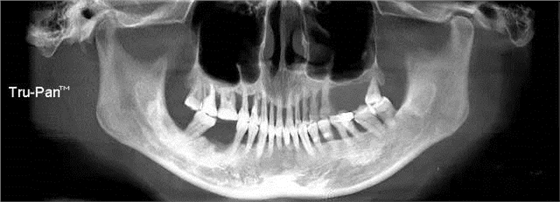

第八圖:有間隔的上頜竇。上頜竇底中間有骨間隔,通常增大了上頜竇外提升開窗的困難。 北一種植老師主張開兩個小窗,有些醫(yī)生也可以開W型窗,來降低難度。